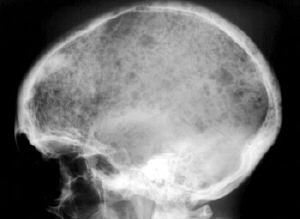

Refer to this picture for question 1. |

1. The following can precipitate or result from the condition shown in

the picture above: